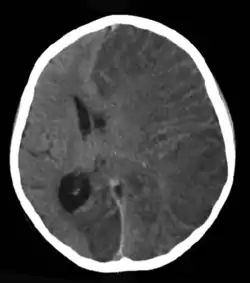

![]() Brain CT scan of a girl with Rasmussen's encephalitis. Brain CT scan of a girl with Rasmussen's encephalitis. | |

قد يتم التشخيص باستخدام الخصائص الإكلينيكية وحدها مع القيام باختبارات لاستبعاد باقي الأسباب المحتملة. يوضح تخطيط أمواج الدماغ عادة الخصائص الكهربية للصرع وبطء نشاط الدماغ في النصف الكروي المصاب، يوضح مسح المخ بالرنين المغناطيسي حدوث ضمور متدرج للنصف الكروي المصاب مع علامات الالتهاب أو تندب. يمكننا تأكيد تشخيص المرض من خلالخزعة دماغية إلا أنها ليست ضرورية بشكل معتاد.